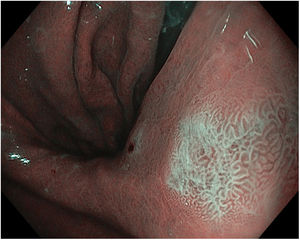

En la figura 2 se observan las características endoscópicas de las lesiones malignas con cada una de las diferentes modalidades anteriormente descritas.

Neoplasia gástrica precoz con histología en toma de biopsias de displasia de bajo grado en curvatura mayor del antro. A)Imagen de luz blanca con alta definición. B)Color violáceo en imagen LCI. C)Imagen BLI. D)Imagen LCI con magnificación. E)Imagen BLI con magnificación. En D y E se observa línea de demarcación periférica y distorsión del patrón superficial y microvascular en su interior.